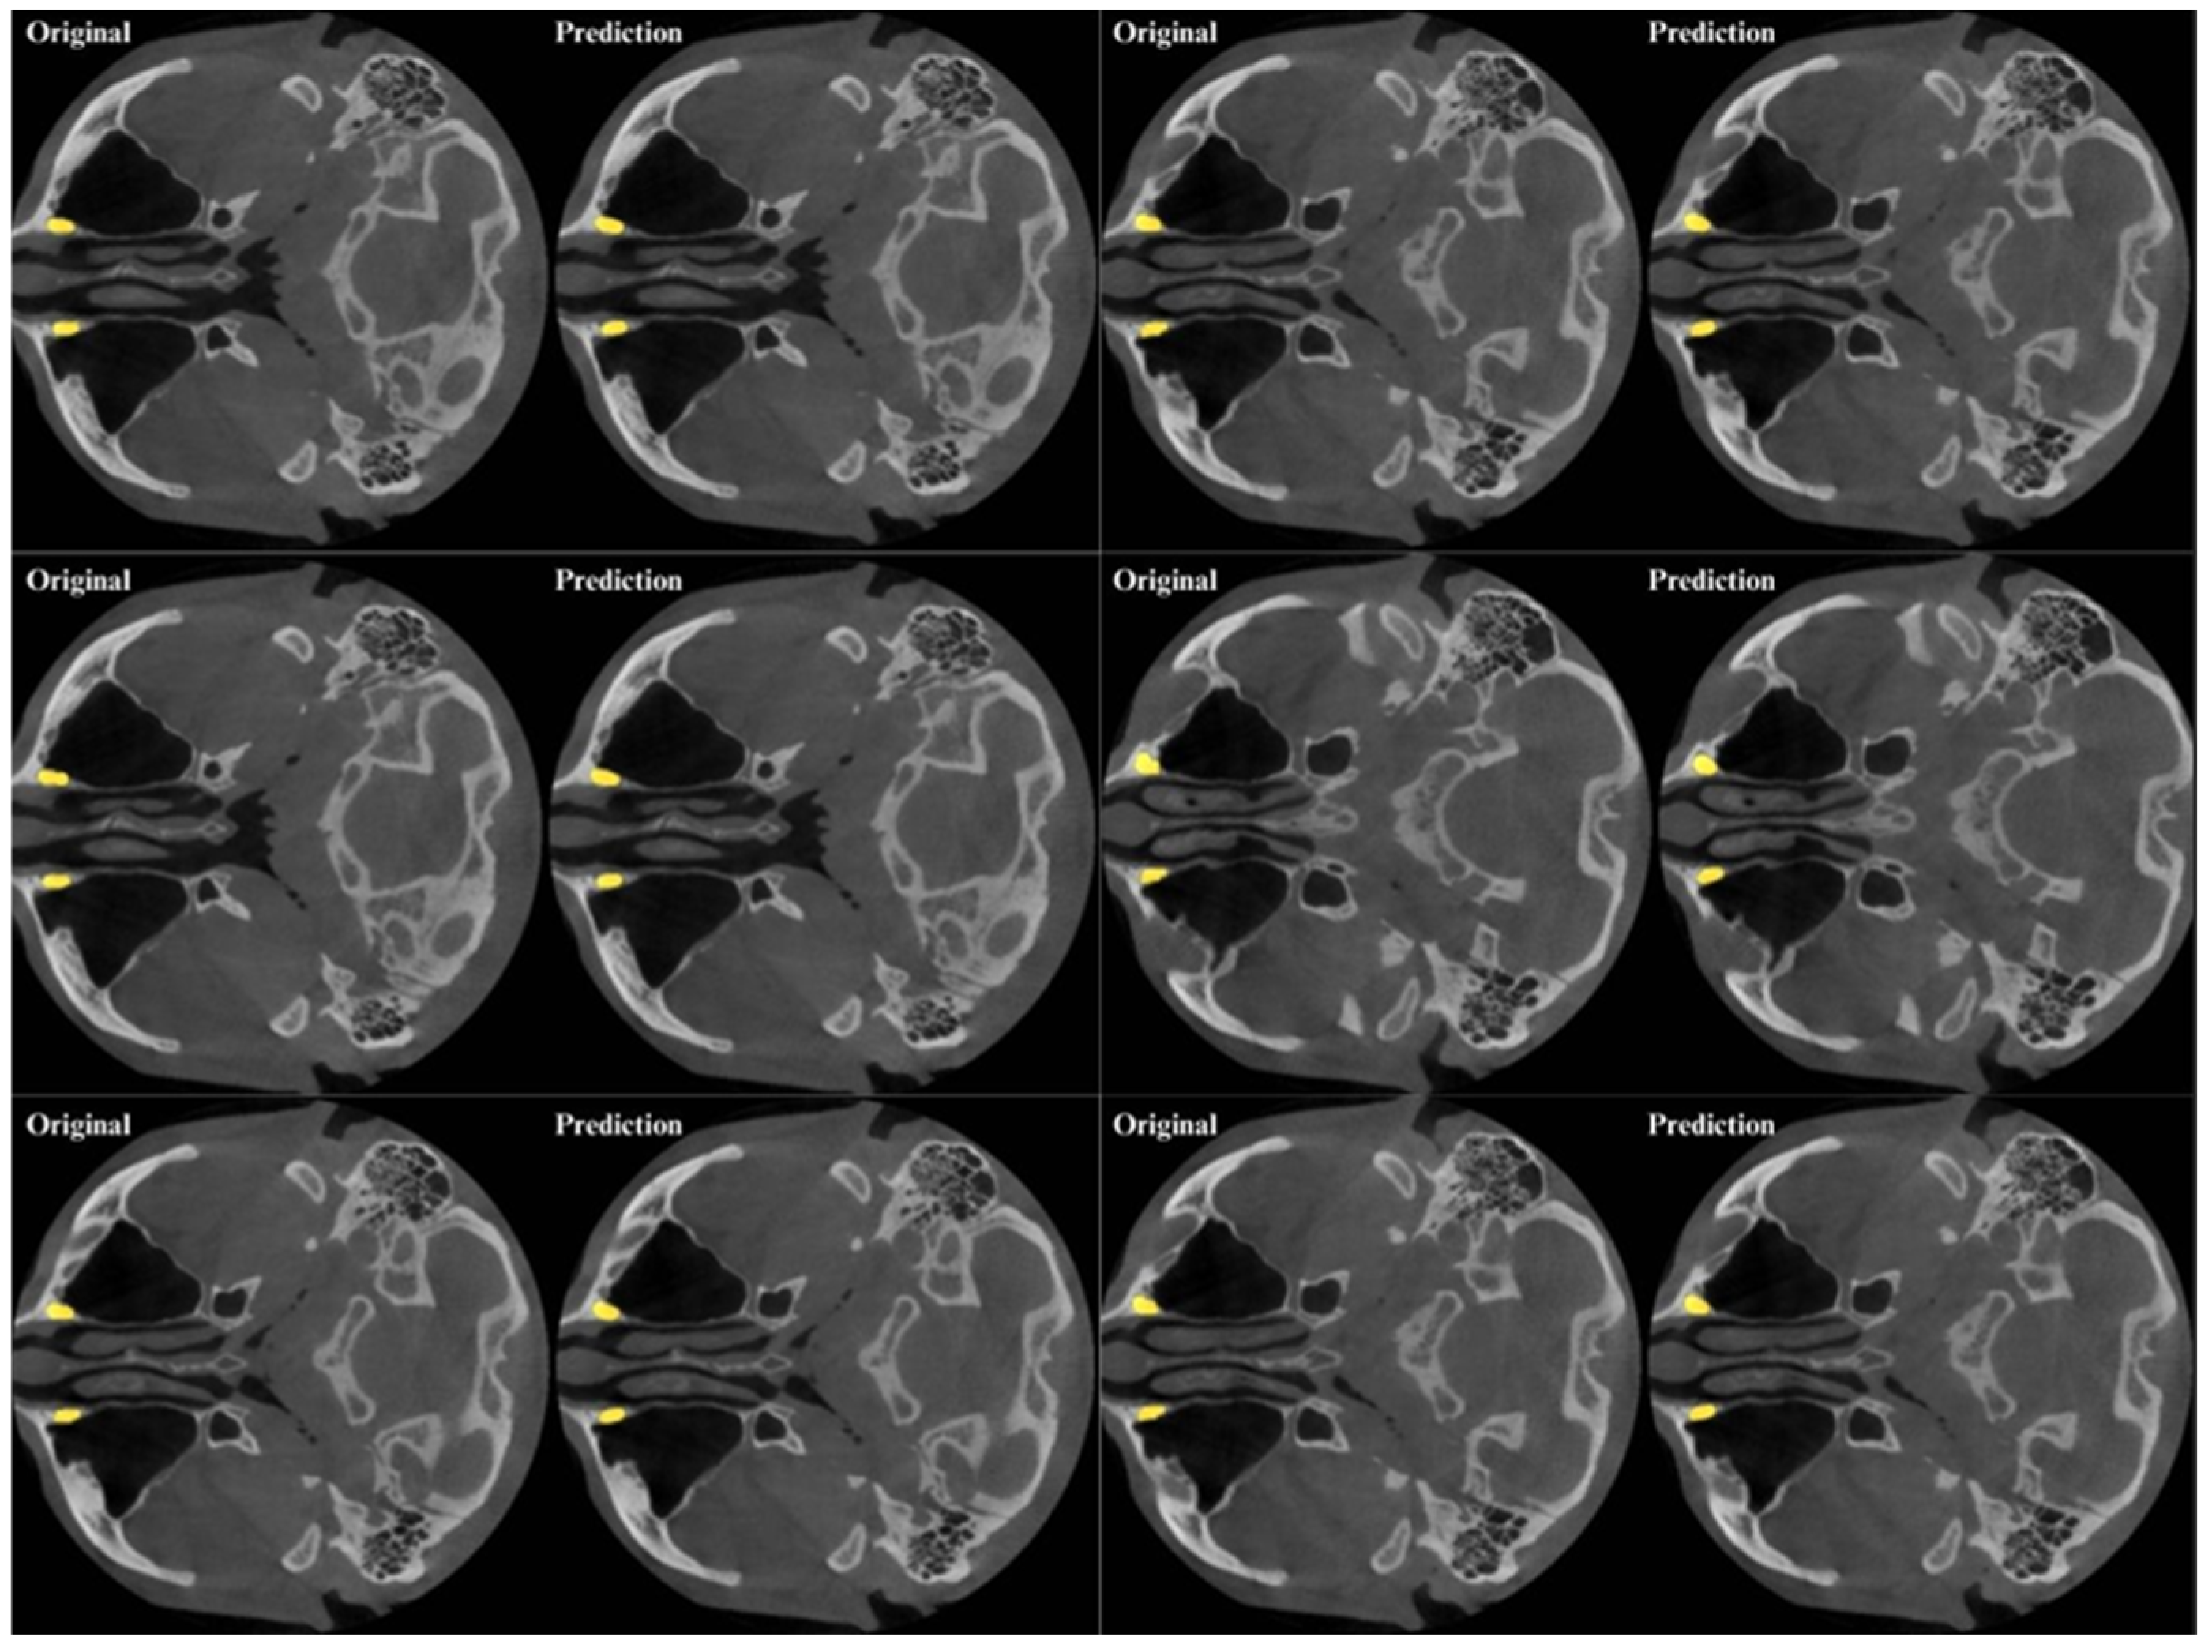

| Metrics | Metric Formula | Metric Value |

|---|---|---|

| True Positive | 16,297.7 | |

| False Positive | 4214.2 | |

| False Negative | 1624.5 | |

| Precision | TP/(TP + FP) | 0.7888 |

| Recall (Sensitivity) | TP/(TP + FN) | 0.9168 |

| Dice Coefficients (DC) | (2 × T P)/(2 × T P + F P + F N) | 0.8465 |

| Intersection over Union (IoU) | (|A∩B|)/(|A∪B|) | 0.7341 |

| F1-Score | 2 × (Precision × Recall)/(Precision + Recall) | 0.8480 |

| 95% Hausdorff Distance (95%HD) mm | dH95(A, B) = max(d95(A, B), d95(A, B)) | 0.9460 |